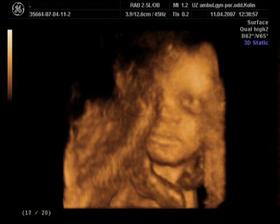

Ve 23.tt jsme se dozvěděli, že čekáme holčičku, už teď se na ní moc těšíme...je to náš poklad a bude se jmenovat ANDREJKA 🙂